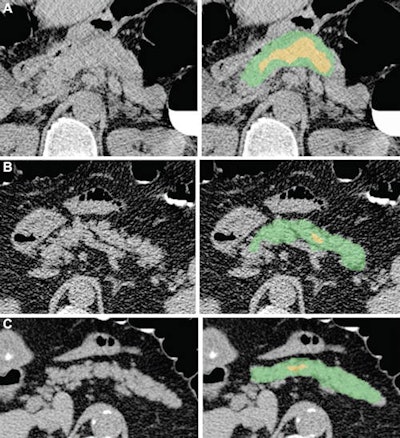

Researchers from the University of Wisconsin School of Medicine and Public Health in Madison, WI, and the U.S. National Institutes of Health (NIH) Clinical Center in Bethesda, MD, developed an automated pancreatic segmentation method for noncontrast CT images. They then tested the algorithm retrospectively on 9,000 consecutive patients who had undergone CTC screening.

In testing on a subset of 25 cases, the deep learning-based pancreas segmentations were deemed to be accurate and reproducible, with a Dice similar coefficient of 0.69 that was equivalent to the interobserver performance for two human readers.